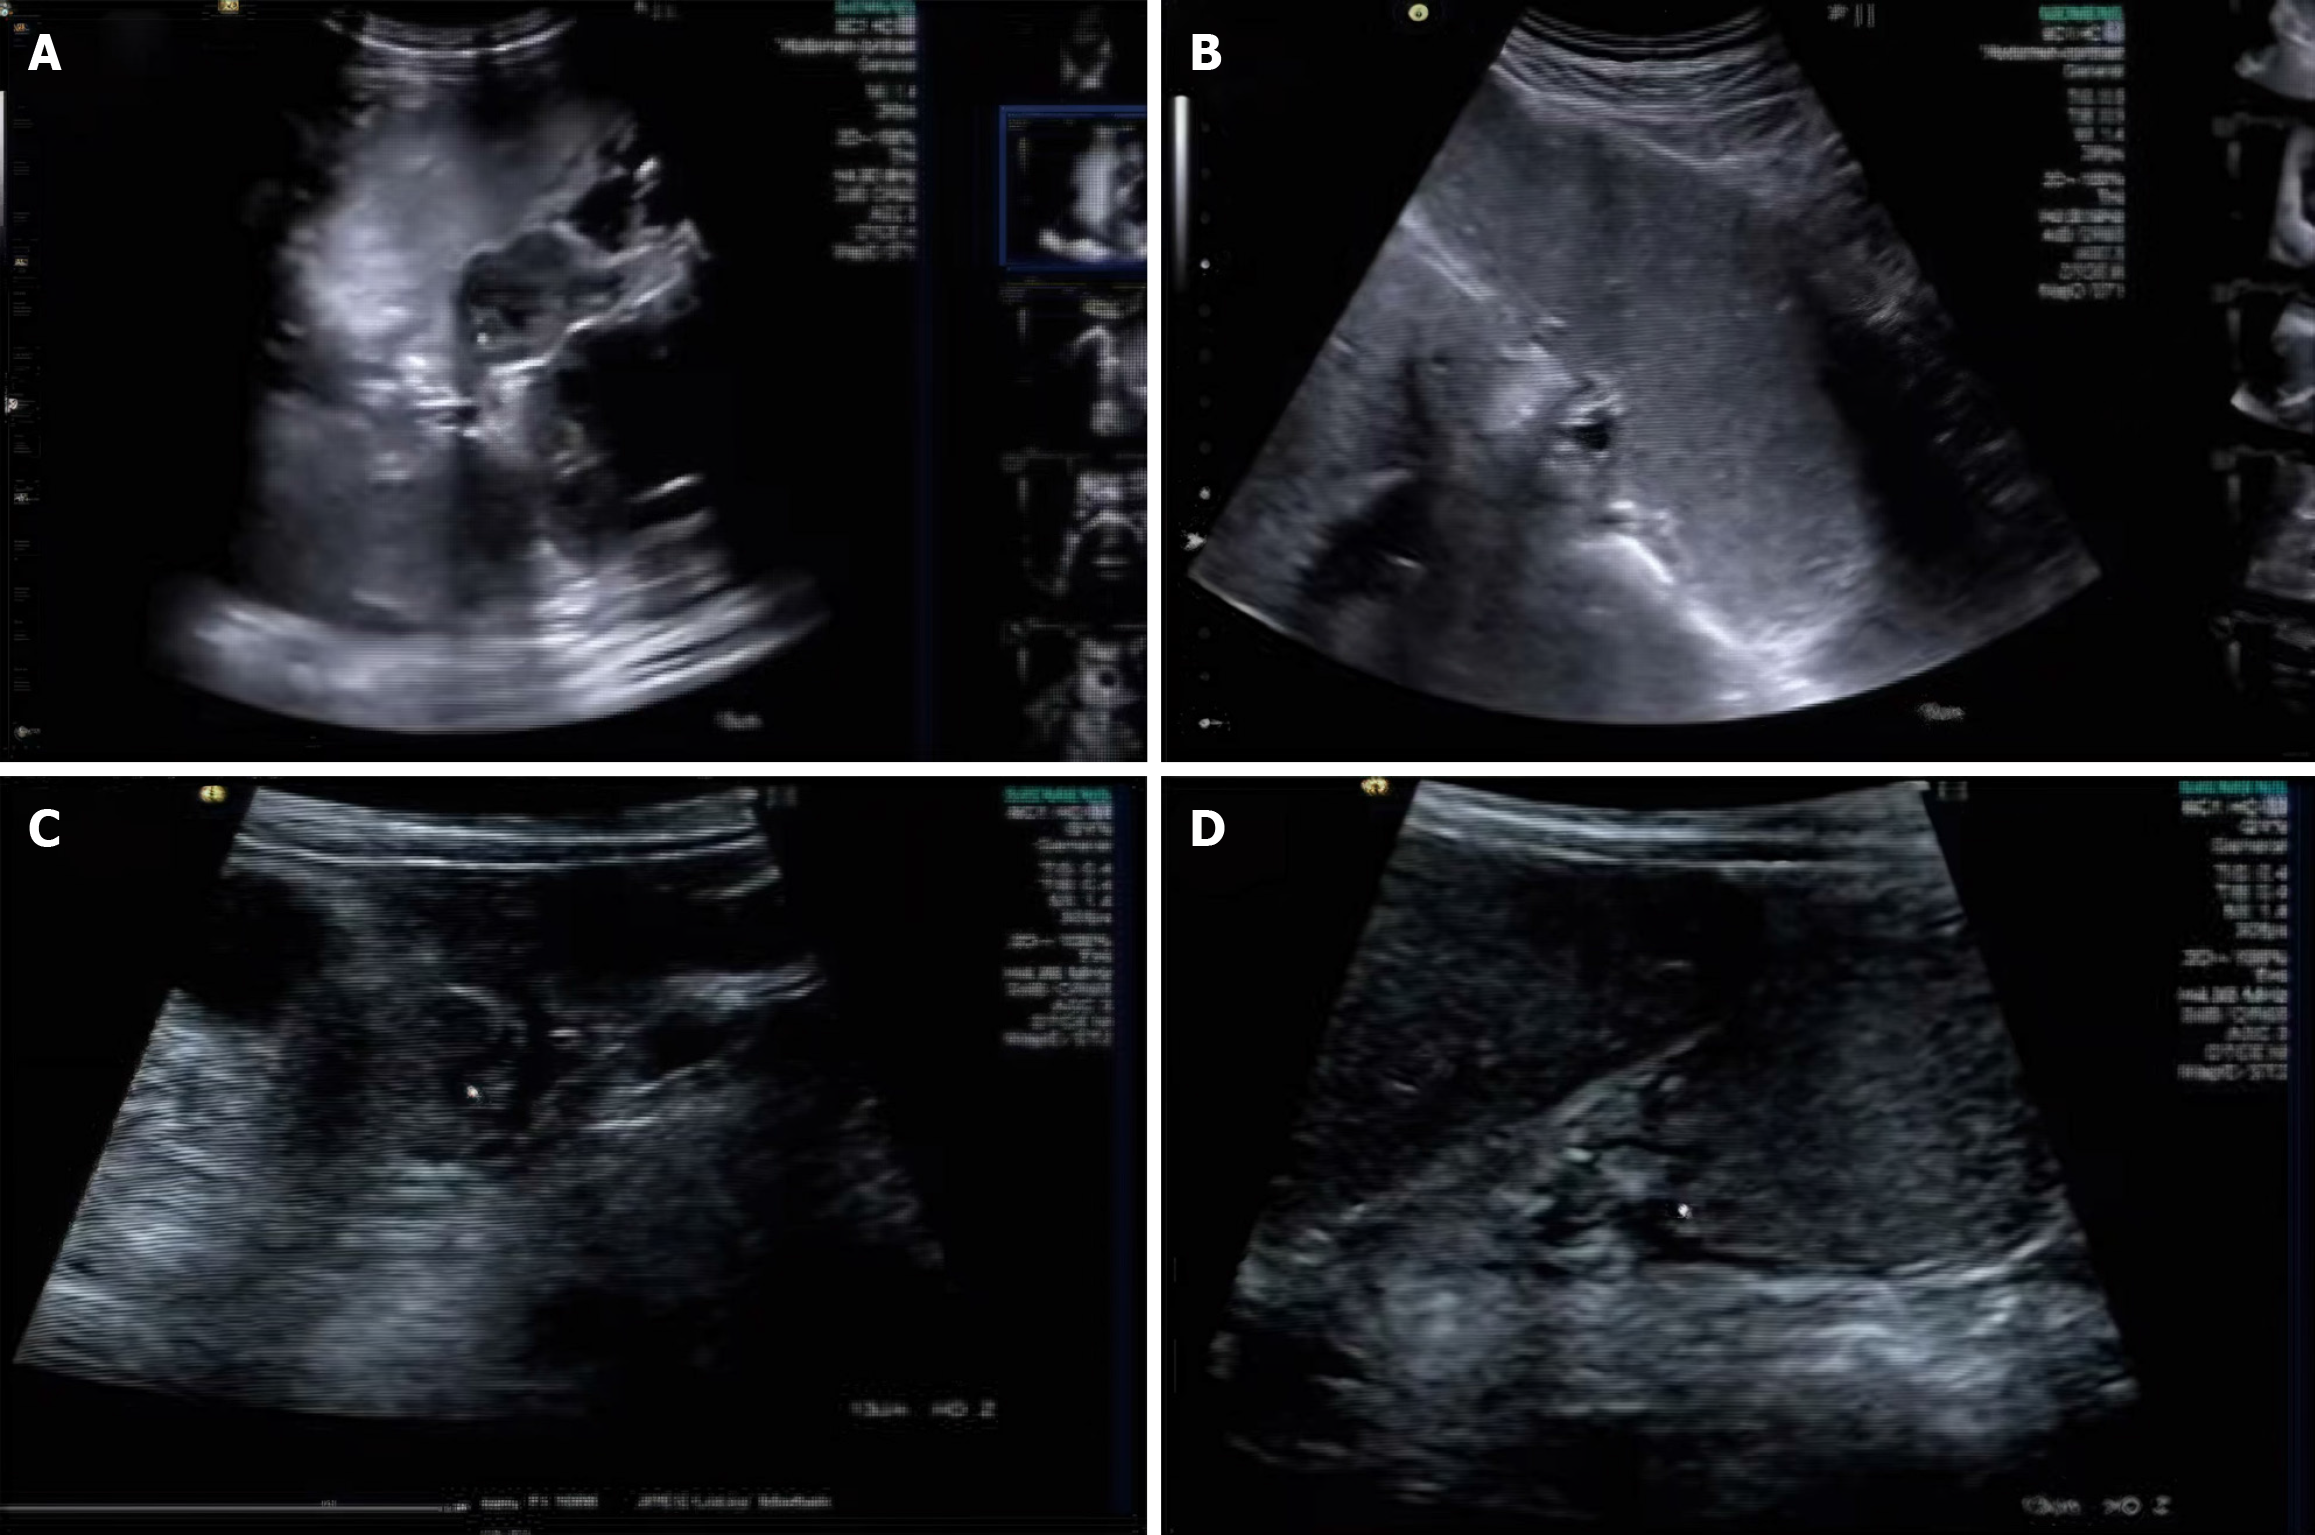

Figure 1 Preoperative gastrointestinal ultrasound localization images.

A: Preoperative gastrointestinal ultrasound localization of tumors in the greater curvature of the stomach; B: Preoperative gastrointestinal ultrasound localization of tumors in the lesser curvature of the stomach; C: Gastric mucosal layer tumor; D: Gastric antral tumor.